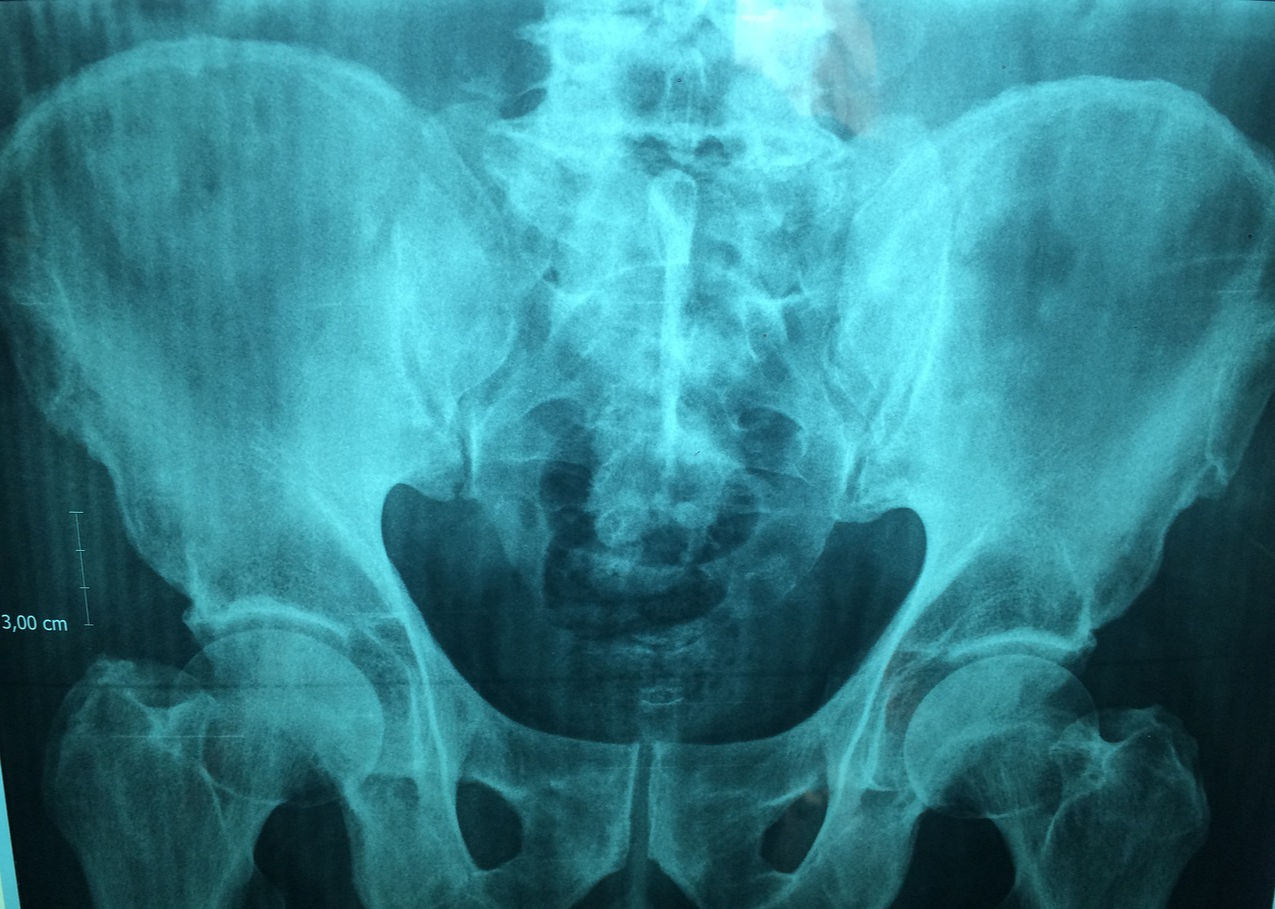

-환자는 등과 엉덩이 또는 손목 부위에 DXA 기계를 이용하여 검사합니다

환자는 검사 대상 부위를 진단하기 위해 적절한 위치로 눕거나 자세를 잡아야 합니다 일반적으로 등과 엉덩이 또는 손목 부위가 검사 대상입니다

DXA 기계의 초점된 X-선 빔이 검사 대상 부위로 쏘아져 뼈를 통과하며 측정합니다 이 과정에서 뼈의 밀도가 측정됩니다